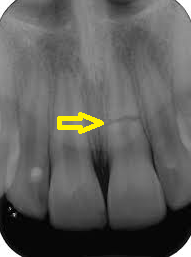

Trauma de concussão Fratura de parte da coroa dentária Frantura da raíz no Raio-x

Exames radiográficos podem ser necessários e alguma contenção temporária até o dente firmar novamente. Dependendo muito da extensão da batida e da mobilidade dentária presente após a batida.

Após todo o atendimento, o paciente deverá ser monitorado por um endodontista. Esse irá avaliar se houve dano ao tecido pulpar (nervo do dente) ou se existe algum risco de reabsorção da raiz do dente afetado. Serão realizados raio-x periódicos para acompanhar a evolução de cada caso.